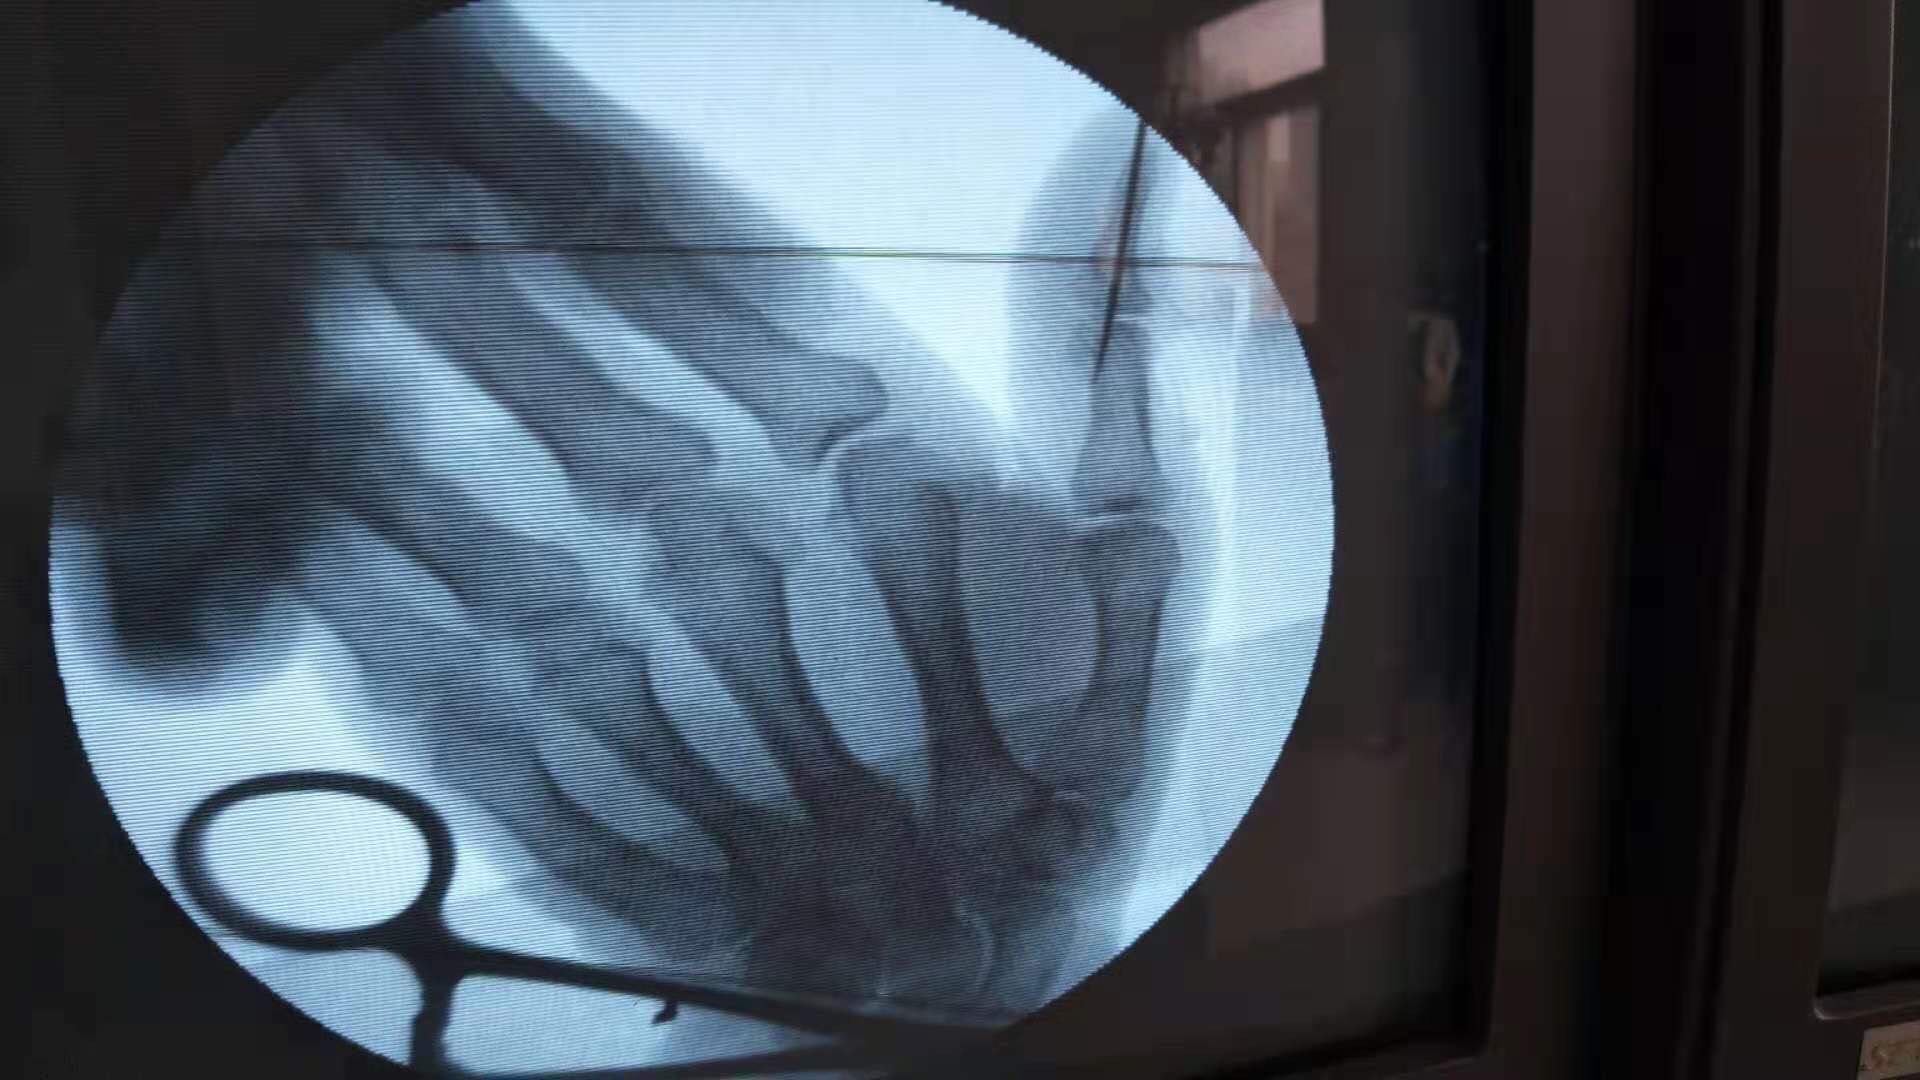

诊断右拇指锤状指在神经阻滞麻醉下切复重建伸指功能,术后抗炎,消肿等处理。